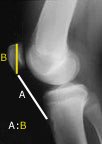

Two ratios have become standard in the assessment of patellar position - these are the Insall-Salvati and Blackburne-Peel vertical height ratios.

Insall-Salvati ratio - length of the patellar tendon (lowest pole of the patella to the tibial tubercle on X-ray) compared to the height of the patella - usually 1.02 +/- 0.2. A ratio of less than 0.8 is considered to be patella infera.

Blackburne-Peel ratio - lowest point on the patellar cartilage to the level of the tibial plateau compared to the length of the patellar articular surface - usually 0.54-1.06. A ratio of less than 0.54 is considered to be patella infera.

In 1991, (ref 2) two colleagues and I compared the two knees of 51 individuals and found that, although the ratio may vary slightly from person to person, it is remarkably consistent between the two knees of the same person. This allowed us to diagnose patella infera by comparing the ratio in the problem knee with that in the normal knee on serial lateral X-rays with the knee in 30-60° of flexion.